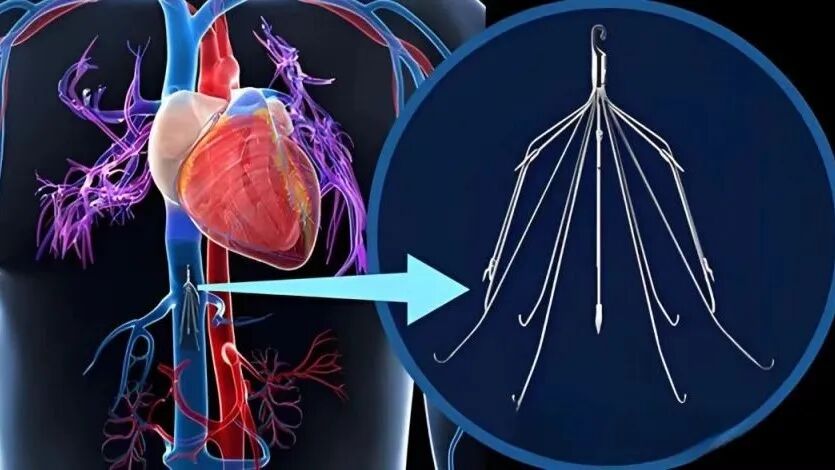

下腔静脉滤器植入术是一种通过介入手段在患者下腔静脉内放置滤器,以防止下肢深静脉血栓脱落并随血流进入肺动脉,造成肺动脉栓塞的手术方法,它就像一个“滤网”,能够拦截可能脱落的血栓,降低肺动脉栓塞的风险。

腿上的血栓脱落后会随静脉血流往上行走,经过腹部到胸部,进入心脏,最终到达肺部(下肢深静脉——髂静脉——下腔静脉——右心房——右心室——肺动脉)。在下腔静脉安置一个过滤器,血流可通过,而血栓被拦截不能通过,就可以完美解除肺栓塞风险。

因此,下腔静脉滤器(IVCF)是为预防下肢深静脉和盆腔静脉丛内血栓脱落引起肺动脉栓塞而设计的一种装置,该装置能在保持下腔静脉血流通畅的同时,可有效拦截血栓,防止肺栓塞的发生。